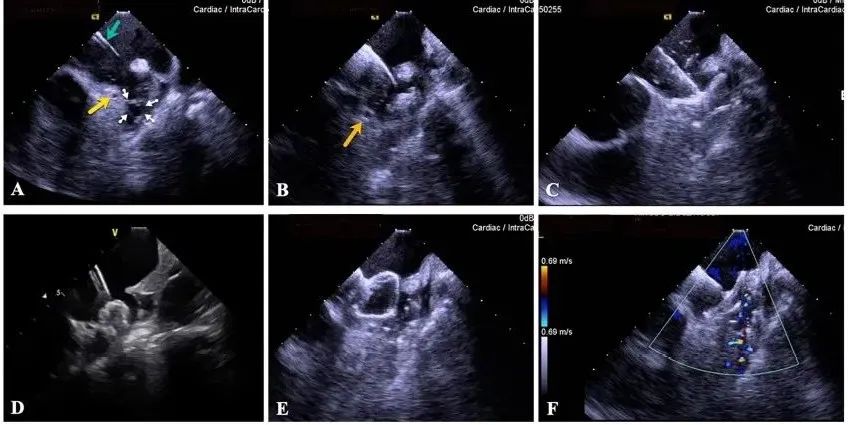

一種與心導管檢查相結合的超聲心動圖診斷新興技術,通過將超聲探頭置于心腔內部,發射并接收超聲信號,來精確獲取心臟解剖結構、心臟血流動力學等信息的實時成像。與其他影像技術相比,ICE技術具有操作簡單、無輻射、安全性高、手術效率高、實用等優勢,ICE在很大程度上有望取代經食道超聲心動圖(TEE),成為電生理和結構性心臟病領域的理想成像方式。

目前ICE技術已被應用于左心耳封堵、房顫射頻消融、二尖瓣成形、房間隔缺損封堵等多種心臟介入手術,應用場景主要圍繞心臟電生理、結構性心臟病等領域,目前以電生理應用為主。數據顯示,我國結構性心臟病介入器械市場規模已從2017年的4億元增長至2021年的20億元,年復合增長率達48.3%;預計到2025年,該市場規模將達到104億元,可以預見ICE市場規模也將同步高速增長,未來市場發展空間廣闊。

心腔內超聲(ICE)技術壁壘極高,國內主要廠商核心部件仍舊為進口,集成了超聲和圖像處理最前端技術,包括超聲探頭、線纜、軟件成像算法等,是當前內窺超聲方向最具挑戰的領域。ICE的應用經歷了2D平面成像、3D三維立體成像、以及4D的實時三維立體成像階段。